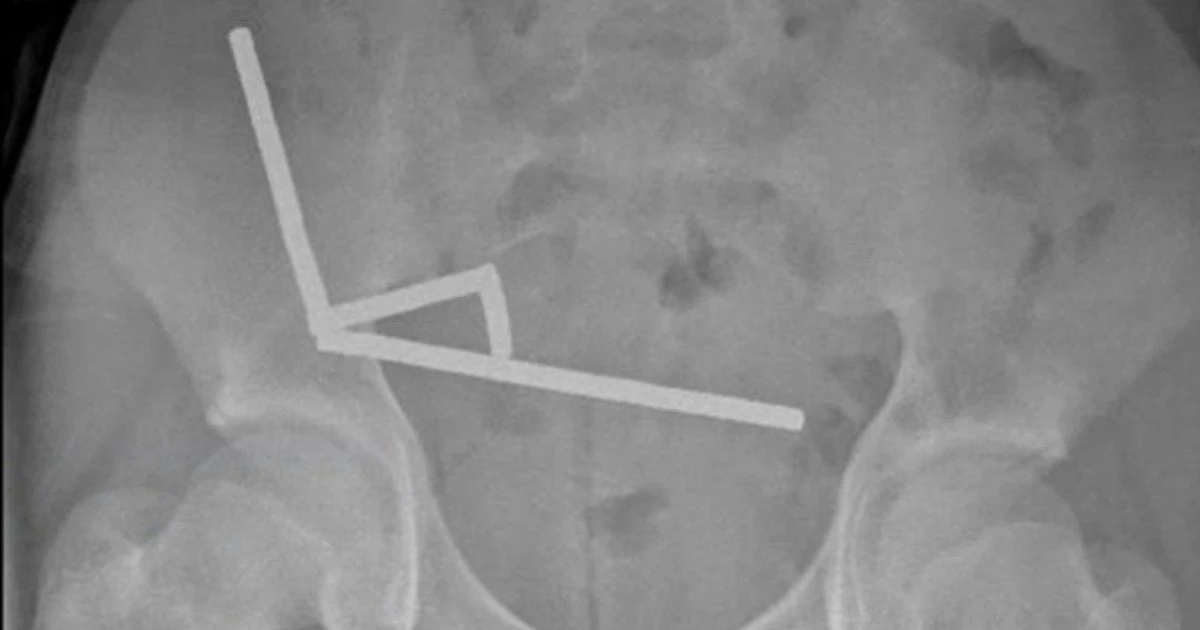

Мальчик четыре дня страдал от боли, прежде чем обратиться за медицинской помощью. Позже он признался, что около недели назад проглотил 80-100 неодимовых магнитов. Он рассказал врачам, что купил их в зарубежном интернет-магазине Temu. Рентген показал, что магниты, запрещённые в Новой Зеландии с 2013 года, образовали «четыре линейные цепочки» в кишечнике.

Врачи, подготовившие отчёт, — Бинура Лекамалаге, Люсинда Дункан-Вере и Никола Дэвис — отметили: «В ходе операции были обнаружены несколько цепочек магнитов в тонком кишечнике и слепой кишке. Они соединились в правом нижнем квадранте, сдавив ткани и вызвав некроз».